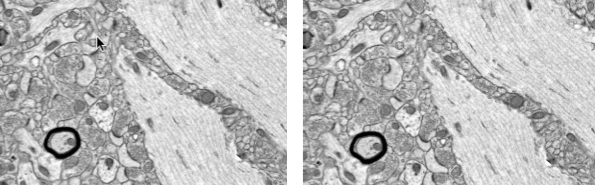

(Left): Control rabbit brain, showing neuropil near the CA1 band in the hippocampus. (Right): Vitrified rabbit brain, same location. Synapses, vesicles, and microfilaments are clear. The myelinated axon shows excellent preservation. (credit: Robert L. McIntyre and Gregory M. Fahy/Cryobiology)

The Small Mammalian Brain Preservation Prize was awarded after the determination that the protocol developed by McIntyre, termed Aldehyde-Stabilized Cryopreservation, was able to preserve an entire rabbit brain with well-preserved ultrastructure, including cell membranes, synapses, and intracellular structures such as synaptic vesicles (full protocol here).

“This is a milestone in the development of brain preservation techniques: it is the first time that the preservation of the connectome has been demonstrated in a whole brain (prior to this only small parts of brains have been preserved to this level of detail),” said the BPF announcement.

“Current models of the brain suggest that the connectome contains all the information necessary for personal identity (i.e., memory and personality). This technique is not the same as conventional cryonics (rapidly freezing the brain), which has never demonstrated preservation of the ultrastructure of the brain. Thus the winning of this prize represents a significant advance in the methods available for large scale studies of the connectome and could lead to procedures that preserve a complete human brain.

Until now, the crucial unanswered questions were “How well does cryonics preserve the brain’s connectome?” and “Are there alternatives/modifications to cryonics that might preserve the connectome better and in a manner that could be demonstrated today?” The Brain Preservation Prize was put forward in 2010 to spur research that could definitively answer these questions. Now, five years later, these questions have been answered: Traditional cryonics procedures were not able to demonstrate (to the BPF’s satisfaction) preservation of the connectome, but the newly invented “Aldehyde-Stabilized Cryopreservation” technique was.

This result directly answers what has for decades been the main skeptical and scientific criticism against cryonics –that it does not provably preserve the delicate synaptic circuitry of the brain. As such, this research sets the stage for renewed interest within the scientific community, and offers a potential challenge to medical researchers to develop a human surgical procedure based on these successful animal experiments.

We describe here a new cryobiological and neurobiological technique, aldehyde-stabilized cryopreservation (ASC), which demonstrates the relevance and utility of advanced cryopreservation science for the neurobiological research community. ASC is a new brain-banking technique designed to facilitate neuroanatomic research such as connectomics research, and has the unique ability to combine stable long term ice-free sample storage with excellent anatomical resolution. To demonstrate the feasibility of ASC, we perfuse-fixed rabbit and pig brains with a glutaraldehyde-based fixative, then slowly perfused increasing concentrations of ethylene glycol over several hours in a manner similar to techniques used for whole organ cryopreservation. Once 65% w/v ethylene glycol was reached, we vitrified brains at −135 °C for indefinite long-term storage. Vitrified brains were rewarmed and the cryoprotectant removed either by perfusion or gradual diffusion from brain slices. We evaluated ASC-processed brains by electron microscopy of multiple regions across the whole brain and by Focused Ion Beam Milling and Scanning Electron Microscopy (FIB-SEM) imaging of selected brain volumes. Preservation was uniformly excellent: processes were easily traceable and synapses were crisp in both species. Aldehyde-stabilized cryopreservation has many advantages over other brain-banking techniques: chemicals are delivered via perfusion, which enables easy scaling to brains of any size; vitrification ensures that the ultrastructure of the brain will not degrade even over very long storage times; and the cryoprotectant can be removed, yielding a perfusable aldehyde-preserved brain which is suitable for a wide variety of brain assays.